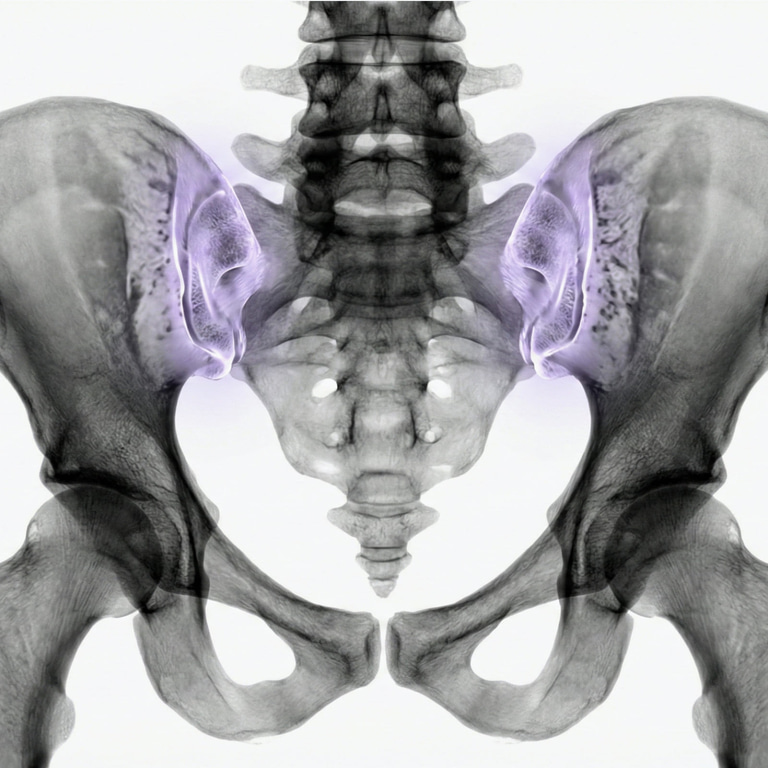

MRI Sacroiliac Joints – Scan for Pelvic, Lower Back or Hip Pain

Pain in the lower back, pelvis or hip may originate in the sacroiliac joints – the two joints that connect the sacrum to the ilium. MRI SI joints are the most sensitive method for detecting inflammation, osteoarthritis, degenerative changes or signs of rheumatic disease in the area.

The examination is particularly valuable in cases of recurrent back and pelvic pain that does not go away with treatment, or in cases of suspicion of inflammatory back disease such as ankylosing spondylitis (Bechterew's disease). MRI can detect early changes that are not visible on X-rays – which is crucial for diagnosis and treatment.